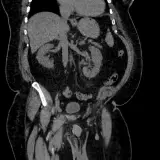

Casos totalmente interactivos con las herramientas que esperaría de un PACS: scroll, ventana, zoom, pan, mediciones, ROI y modo de pantalla completa.

• Anotaciones enlazadas

Anotaciones extensas resaltan los hallazgos clave directamente sobre los casos. Haga clic en los hallazgos enlazados dentro de la descripción del caso para saltar a su ubicación exacta en el estudio.